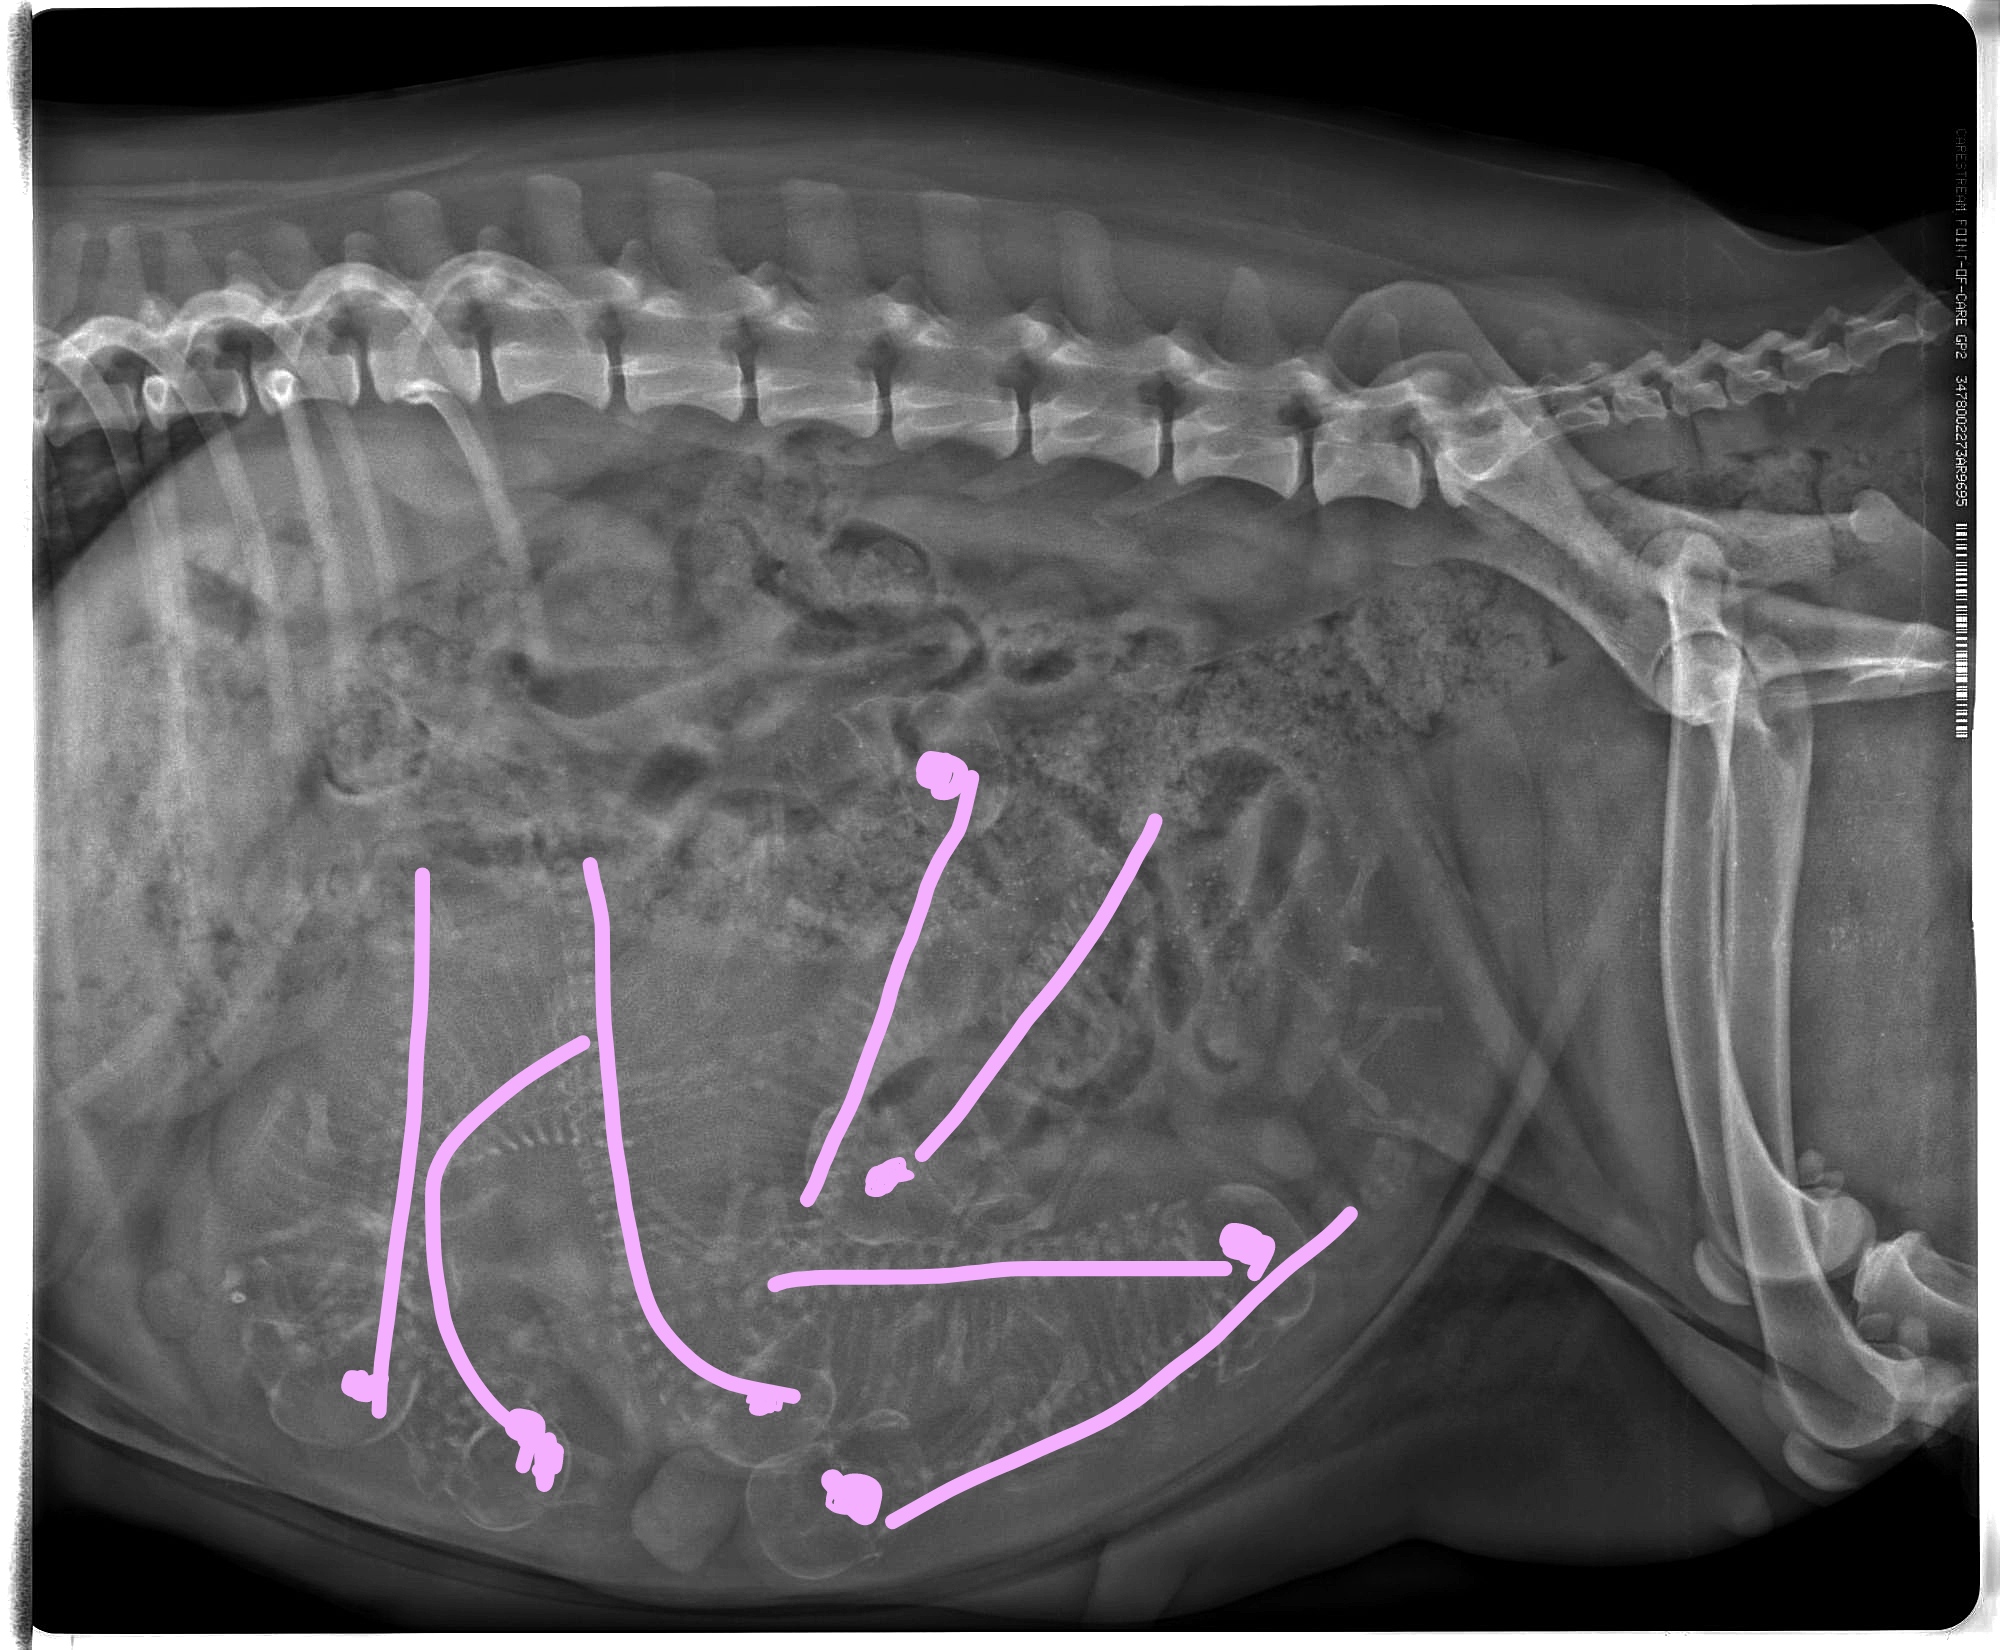

So nun die Innenaufnahme von Emmas Bauch. Einmal normal und einmal etwas bearbeitet und eingezeichnet. was wir gesehen haben. Also wer auf 7 gekommen ist beim zählen war sehr gut. Obwohl die Tierärztin einen 8. bei dem Knochensalat nicht ausschließen will. Dazu wollte Emma an den morgen auch absolut nicht kacken. Wir waren gleich früh um 8 Uhr dran, wir sind nach dem Röntgen dann aus der Praxis und Emma hat erstmal einen großen Haufen vor dem Fenster der Praxis gemacht, ob sie der Tierärztin damit was sagen wollte? Aber eine zweite Aufnahme wollten wir dann auch nicht mehr machen. Die Bauchzwerge sind alle ziemlich gleichmäßig entwickelt. Und von der Größe her dürfte es keine Probleme bei der Geburt geben, die Köpfe sind im Vergleich zum Becken nicht sehr groß. Aber die Größe ist halt nur ein Aspekt, der andere ist die Lage und leider können sie sich auch gegenseitig behindert bei der Geburt, aber wir hoffen nun alle das Beste. Emma wird froh sein, wenn die Welpen endlich da sind, die Wärme macht ihr teilweise schon ziemlich zu schaffen, sie liegt am liebsten da wo es kühl ist. Sie mag auch vom Nervzwerg Hexe nicht mehr allzuviel wissen. Momentan muss da Kiwi mehr erhalten. Ansonsten warten wir jetzt der Dinge die da kommen werden.

Ich war heute mit Emma beim Röntgen, leider hat mir die Tierärztin bisher das Bild nicht geschickt und ich will Euch den Spaß nicht nehmen selbst zu suchen. Daher gibt es noch keine Auflösung wieviele Welpen Emma bekommt.

Emma hat bisher 4,5kg zugenommen, noch ist etwa 1 Woche bis zur Geburt. Man sagt dass, die Mutterhündin für jeden Welpe bis zur Geburt circa 600-800g zunimmt. Und ich denke mal ein paar Gramm wird sie auch noch draufpacken... Wer gut in Mathe ist kann ja vielleicht auch schon errechnen wieviele es sind. ;) Obwohl 100% sicher waren wir uns beim Röngten auch nicht. Emma wollte vor dem Röngten partout nicht kacken.